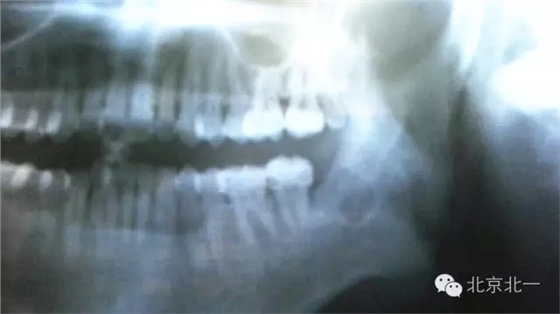

圖一:全景片可見下頜骨下緣高密度影像,清晰可見。